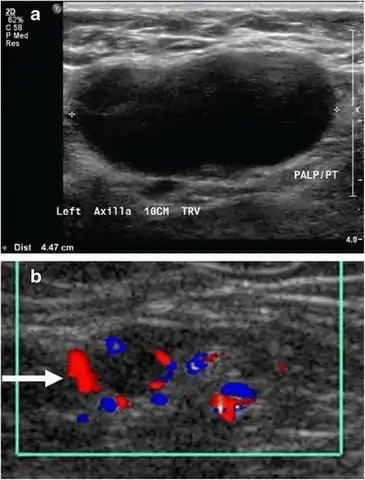

Medical ultrasonography of a typical normal lymph node: smooth, gently lobulated oval with a hypoechoic cortex measuring less than 3 cm in thickness with a central echogenic hilum.[25]

Ultrasonography of a suspected malignant lymph node:

- Absence of the fatty hilum

- Increased focal cortical thickness greater than 3 cm

- Doppler ultrasonography that shows hyperaemic blood flow in the hilum and central cortex and/or abnormal (non-hilar cortical) blood flow.[25]

On ultrasound, B-mode imaging depicts lymph node morphology, whilst power Doppler can assess the vascular pattern.[27] B-mode imaging features that can distinguish metastasis and lymphoma include size, shape, calcification, loss of hilar architecture, as well as intranodal necrosis.[27] Soft tissue edema and nodal matting on B-mode imaging suggests tuberculous cervical lymphadenitis or previous radiation therapy.[27] Serial monitoring of nodal size and vascularity are useful in assessing treatment response.[27]

Lymphadenopathy of the axillary lymph nodes can be defined as solid nodes measuring more than 15 mm without fatty hilum.[35] Axillary lymph nodes may be normal up to 30 mm if consisting largely of fat.[35]